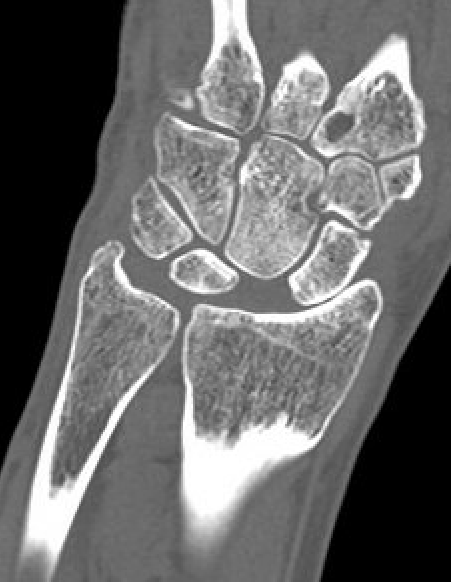

CT

MRI

SL ligament injury with minimal disassociation / SL separation / dynamic instability

SL ligament injury with SL separation and static instability

Increased scapholunate angle